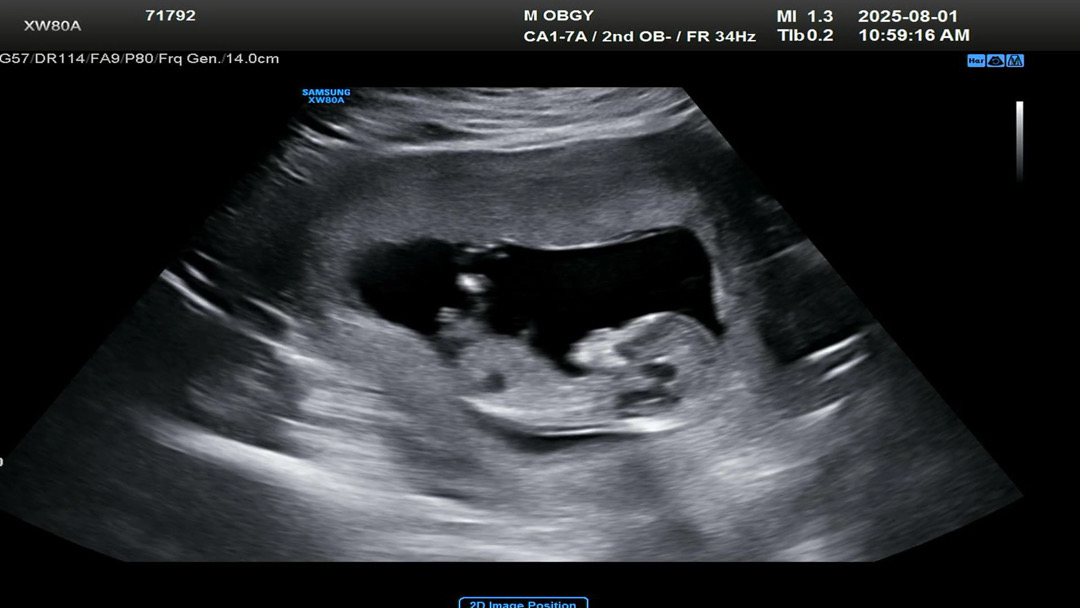

저 각도법 봐주세요🥹

아들,딸,,각도법 잘 보시는분 알려주세용

지금 사진에서 성기 각도가 안보여요 배에 튀어나온건 저거 탯줄이에요

음 아들같아요